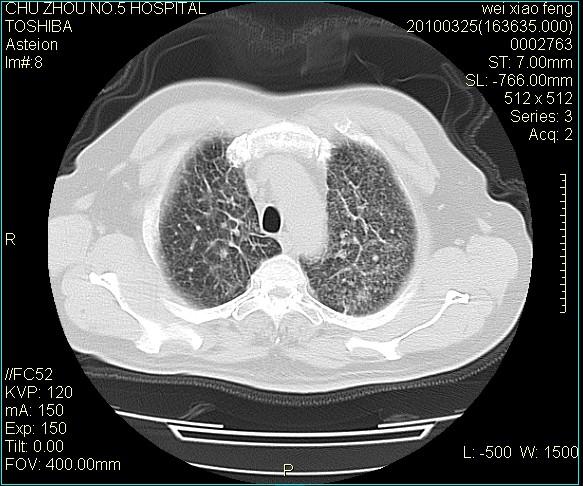

标题: CT25347:男,60岁,反复咳、痰、喘3月,加重3天。诊断??? [打印本页]

男,60岁,反复咳、痰、喘3月,加重3天。

双肺间质性改变。

考虑双肺血型潘散肺结核/

间质性肺炎伴间质纤维化!不排除伴有职业病!

考虑尘肺

间质病变,间质炎症,间质纤维化趋势